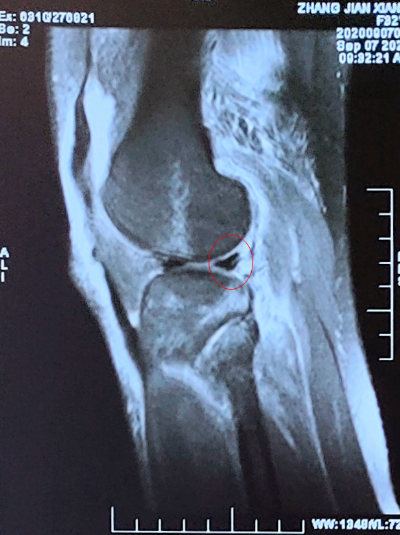

MRI可见:内侧副韧带股骨止点撕裂(红圈所示)